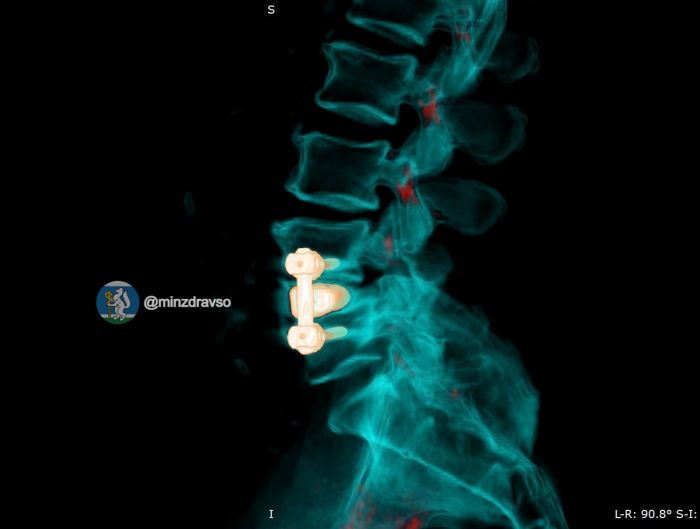

Сначала нейрохирурги удалили инфицированную конструкцию и выполнили санацию очага воспаления. Далее пациент прошёл курс интенсивной антибактериальной терапии и предоперационной подготовки. После мужчине установили титановый 3D-имплант, изготовленный по его индивидуальным анатомическим параметрам, а фиксацию позвоночника выполнили российскими спонгиозными винтами.

В первые сутки после второй операции у пациента полностью прошли все боли. Мужчина сумел встать на ноги и начал ходить без помощи. Сейчас он проходит реабилитацию и готовится к выписке.